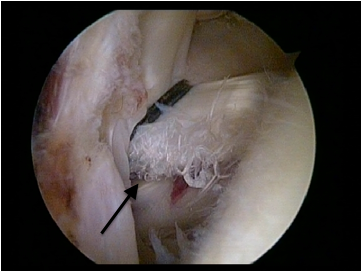

The Snapping Scapula: Diagnosis And Treatment

The Snapping Scapula: Diagnosis and Treatment LT Michael Kuhne, M.D., M.C., U.S.N., Nicole Boniquit, In most cases overuse injuries and repetitive strains by repetitive shoulder girdle stress and overhead arm ... Read Here